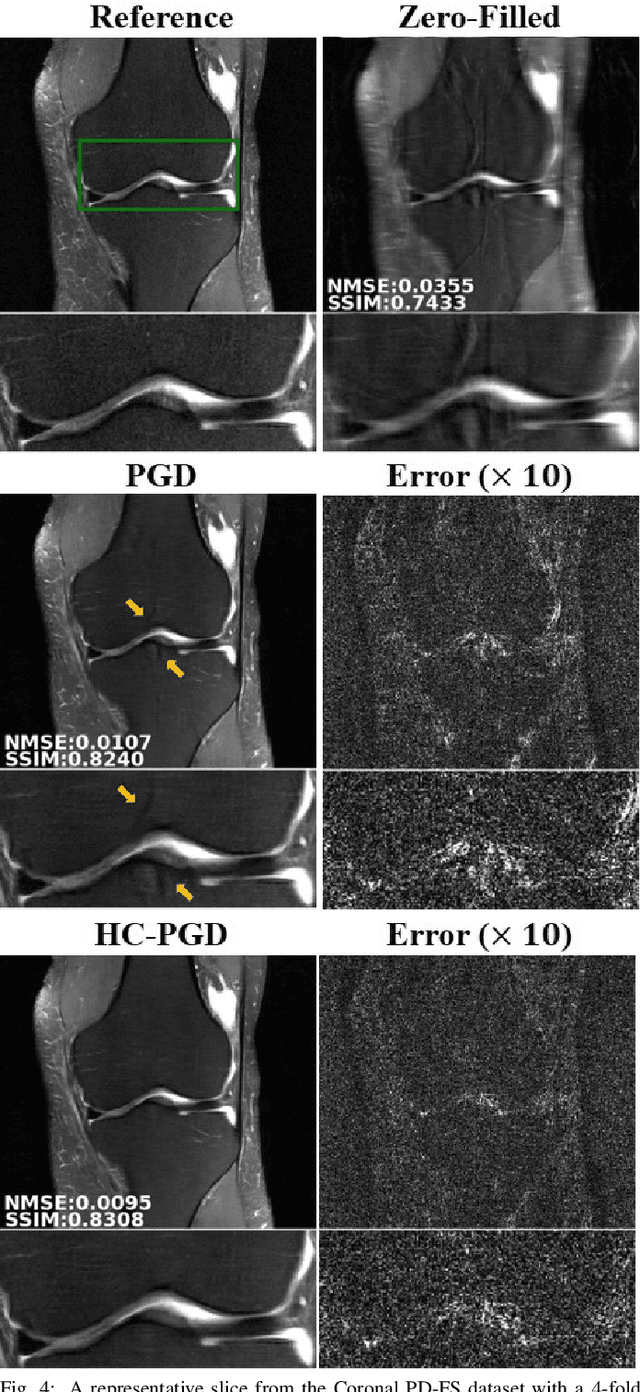

Abstract:Inverse problems in medical imaging applications incorporate domain-specific knowledge about the forward encoding operator in a regularized reconstruction framework. Recently physics-driven deep learning (DL) methods have been proposed to use neural networks for data-driven regularization. These methods unroll iterative optimization algorithms to solve the inverse problem objective function, by alternating between domain-specific data consistency and data-driven regularization via neural networks. The whole unrolled network is then trained end-to-end to learn the parameters of the network. Due to simplicity of data consistency updates with gradient descent steps, proximal gradient descent (PGD) is a common approach to unroll physics-driven DL reconstruction methods. However, PGD methods have slow convergence rates, necessitating a higher number of unrolled iterations, leading to memory issues in training and slower reconstruction times in testing. Inspired by efficient variants of PGD methods that use a history of the previous iterates, we propose a history-cognizant unrolling of the optimization algorithm with dense connections across iterations for improved performance. In our approach, the gradient descent steps are calculated at a trainable combination of the outputs of all the previous regularization units. We also apply this idea to unrolling variable splitting methods with quadratic relaxation. Our results in reconstruction of the fastMRI knee dataset show that the proposed history-cognizant approach reduces residual aliasing artifacts compared to its conventional unrolled counterpart without requiring extra computational power or increasing reconstruction time.